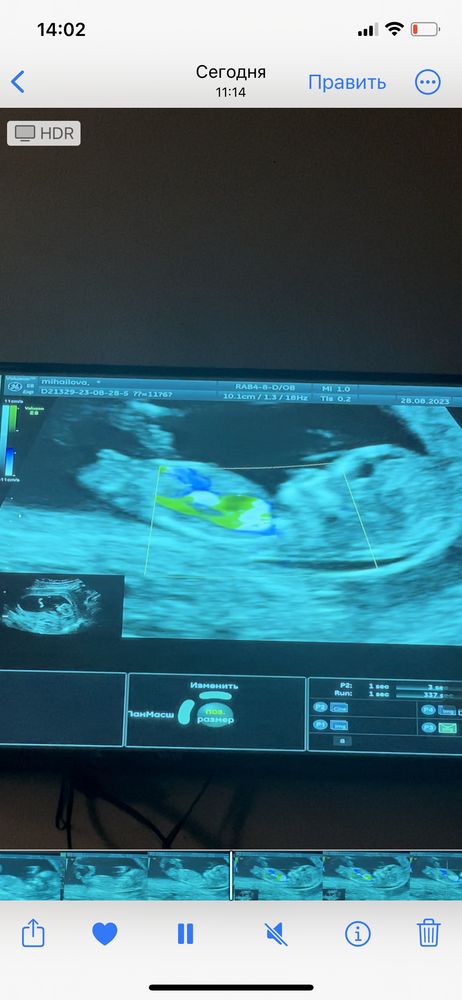

Кто расшифрует показатели по скринингу и пол малыша?🙈 Была сегодня на скрининге 🥹 срок по узи и месячным день в день. Пол сказала узистка даже смотреть не будет, как я не просила, сказала она мне терпеть 🥲 отправлю замерчики😁 правда они на укр языке. Посмотрите знающим глазом 😁🫂 и может кто по фото поймёт пол малыша, интерес берет своё

Добрый день, если есть узи на 7-8 неделе, то можно посмотреть по тесту Рамзи, на этом скрининге нужно смотреть под каким углом находится половой бугорок.

Настенька, ну по этому узи у вас девочка) Так как если фото узи перевернуть, то эмбрион будет слева, а слева по тесту Рамзи закреплены девочки, у меня совпало. Единственное у меня полукруг был вверху, а у вас на фото внизу, не знаю, зависит ли от него расположение эмбриона или нет.

Генриетта , а вот здесь можно посмотреть по половому бугорку, тут у вас тоже похоже на девочку.